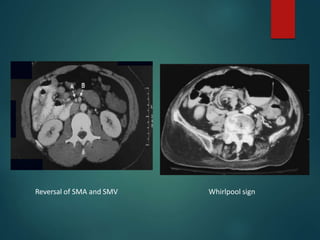

CT Abdomen • Anatomiclocation of small bowel on right and colon on left • Relationship of the superior mesenteric vessels – “vertically placed or inverted sides” • Aplasia of the uncinate process • Features of volvulus / obstruction / gangrene • Other associated anomalies

Reversal of SMAand SMV Whirlpool sign